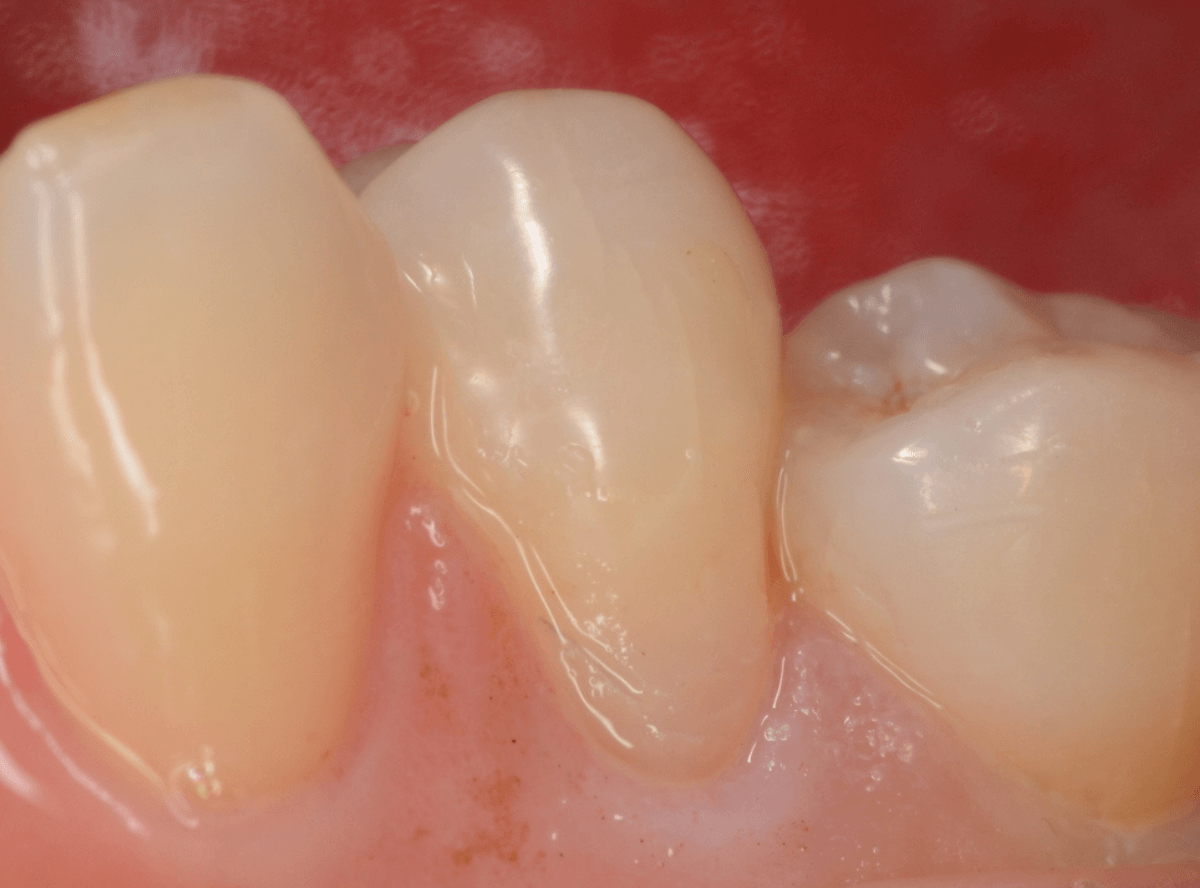

Case.3

「歯の側面が虫歯になってしみる」という訴えで来院された患者さんです。

これは、くさび状欠損といって、歯ブラシ圧の強すぎや歯ぎしりなどが原因で歯の側面が摩耗した状態の部分が若干の虫歯になった状態です。

くさび状欠損は、知覚過敏の原因になる事が多いですが、症状がなければ経過観察にする事も多いです。

今回は、表面が虫歯になっている事と、しみるという症状があるため、治療をする事になりました。

麻酔をして、虫歯の部分を除去します。

幸い、表面上の虫歯でしたので、歯の削除量は少なく済みました。

削った部分にレジンを充填して終わりです。

これでしみる症状は改善されると思いますが、麻酔をしているので、確認は次回来院時になります。